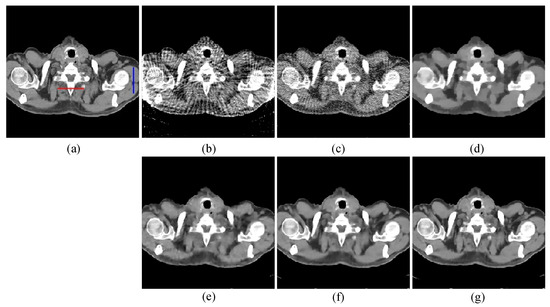

The first image reconstruction experiment is using a pelvic image to show the feasibility of our algorithm for SVCT reconstruction, as shown in Figure 1. We extracted 80, 64, and 48 views from a full scan and selected parameters empirically. The parameters are set as follows: a = 0.5, γ1 = 0.3, and γ2 = 0.08. Figure 2, Figure 3 and Figure 4 show the ground truth and reconstruction images via FBP, OS-SART, TV, PICCS, TVPI-G, and our method NPICCS. From these figures, it is evident that our algorithm outperforms the other methods in terms of recovering image structures and suppressing noise. Specifically, the FBP and OS-SART results (as shown in Figure 2b,c, Figure 3b,c and Figure 4b,c) contain high levels of noise and artifacts, while TV results (as shown in Figure 2d, Figure 3d and Figure 4d) are characterized by blurring and staircasing effects. The PICCS and TVPI-G methods provide better results than the other approaches because of the introduction of prior information, but image edges are missing as shown in Figure 2e,f, Figure 3e,f and Figure 4e,f. At the same time, it can be seen that our method is able to preserve image edges and suppress noise effectively, as shown in Figure 2g, Figure 3g and Figure 4g.

Figure 3. 64 views reconstruction results of pelvic image: (a) ground truth, (b) FBP, (c) OS-SART, (d) TV, (e) PICCS, (f) TVPI-G, and (g) NPICCS. The display window is [−150 250] HU.